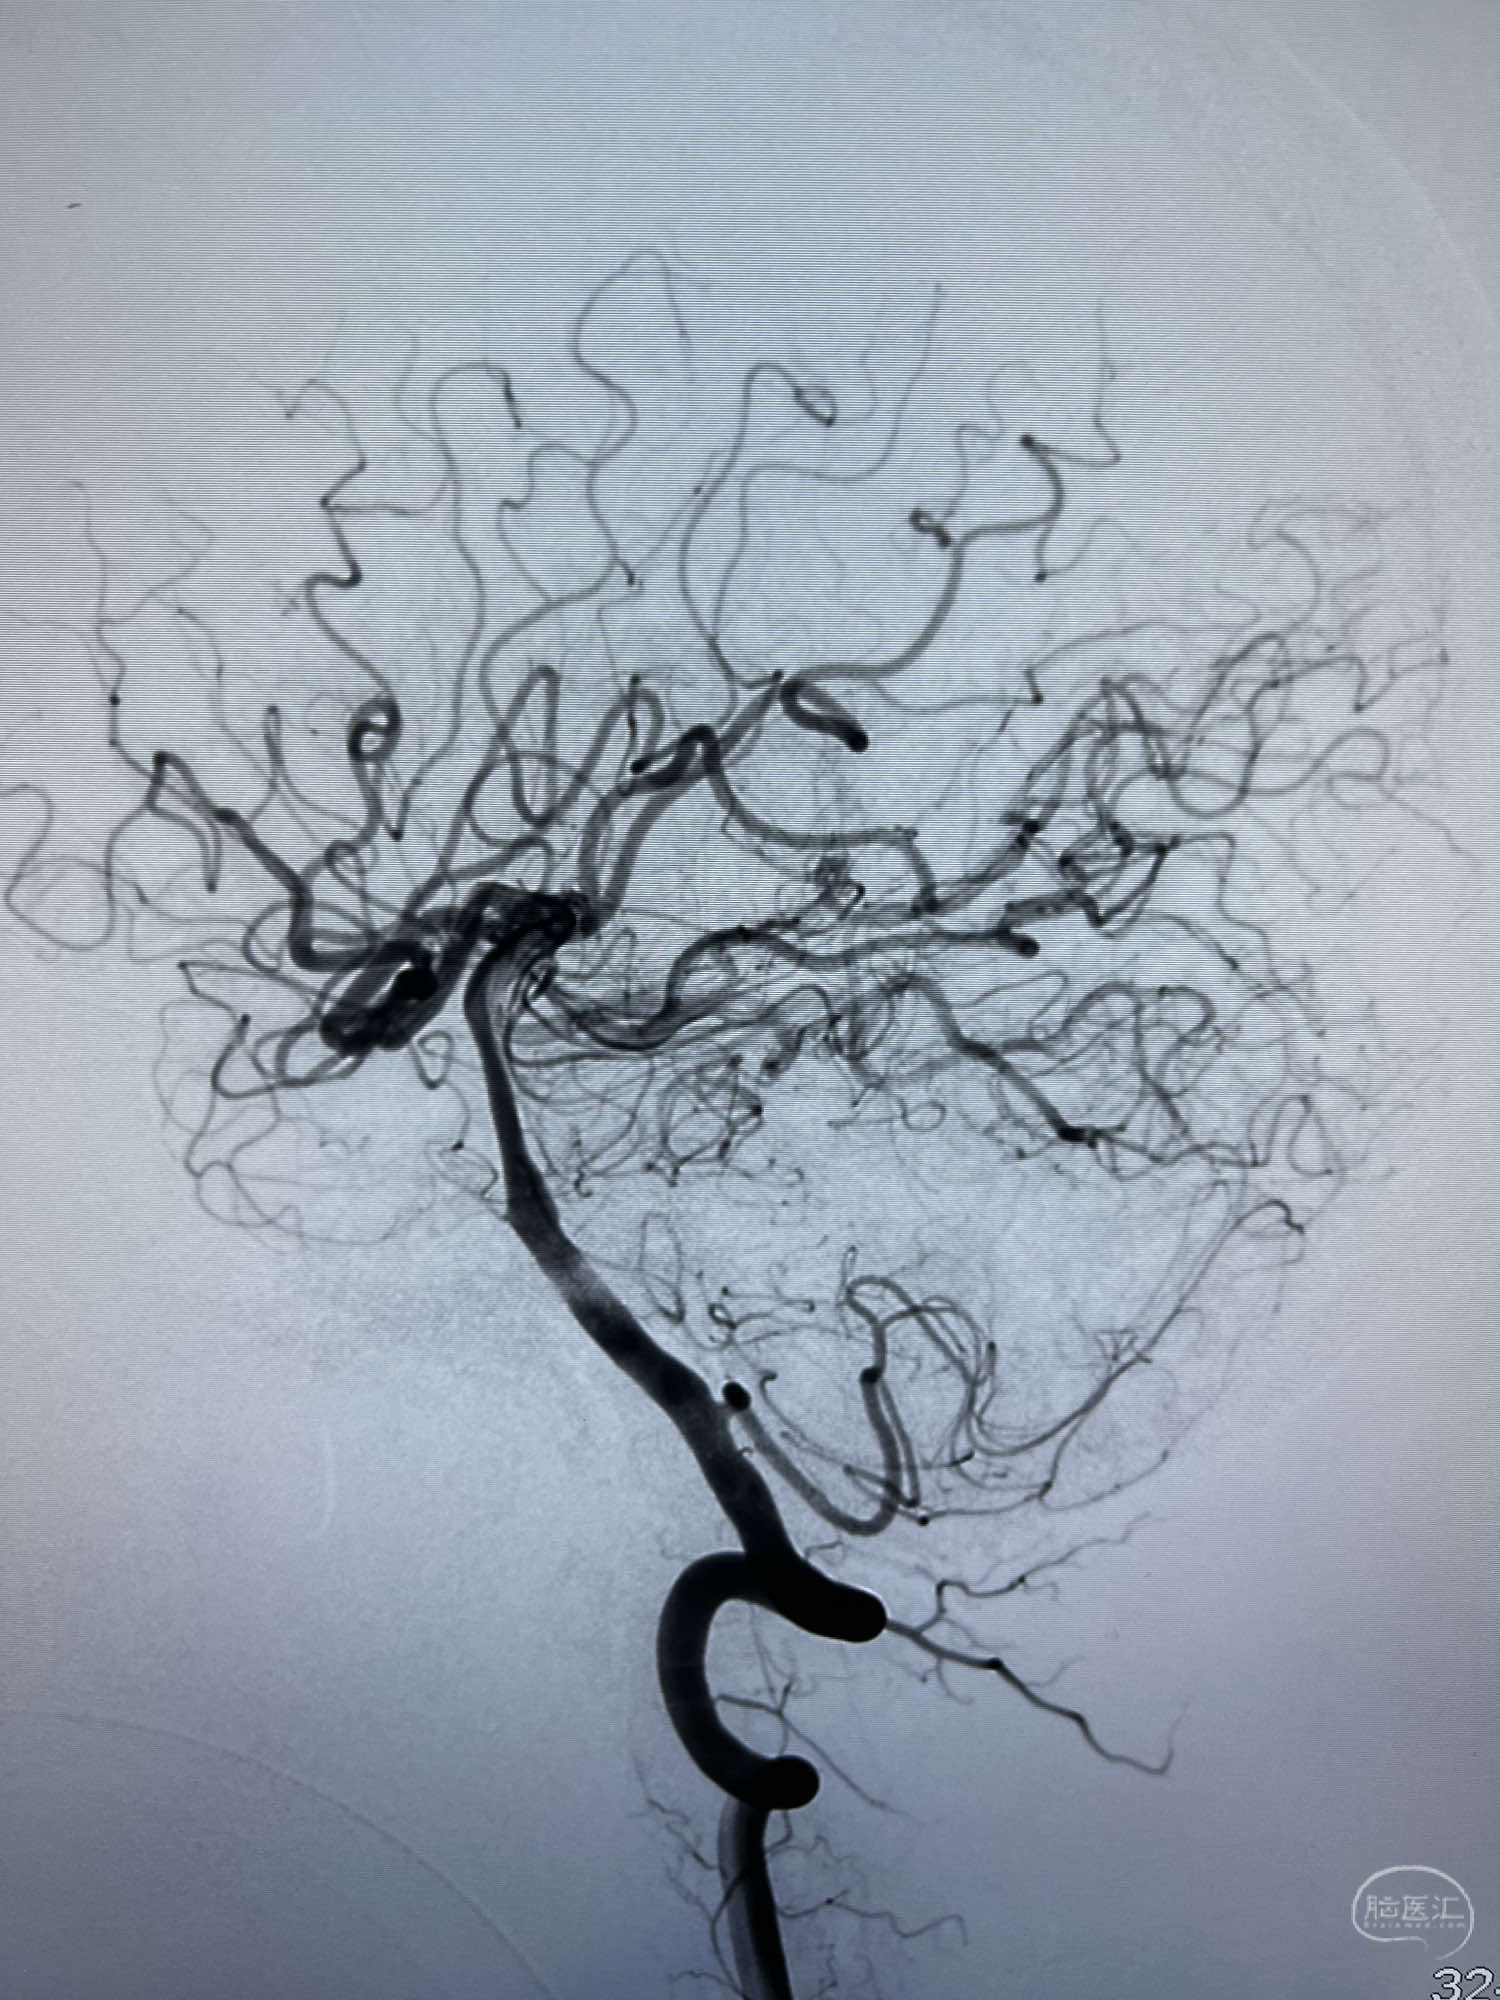

6F Neuromax➕6F115cm 心玮中间导管建立路径,sychro14微导丝➕VIA21超选至动脉瘤体内近中部,WEB5mmx3mm植入动脉瘤。

WEB瘤内扰流装置5mmx3mm经过“种子、萌芽、开花”三个阶段,打开后良好贴壁,动脉瘤内血液滞留,载瘤动脉通畅。WEB一步到位,通过瘤内扰流的方式起到栓塞动脉瘤的作用,避免了应用支架保护分支血管,简化了操作步骤,降低了术中血栓及出血的风险。